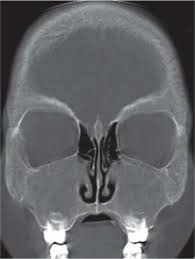

Is your nose also an excretory organ? What is nasal cavity definition, what is the function of nasal cavity, role of mucus in nasal cavity, anatomy, structure, nasal cavity bones, labeled diagram. Introduction:the nasal cavities are the uppermost parts of the. The nasal cavity (or nasal fossa) is a large air filled space above and behind the nose in the middle of the face. The nasal cavity anatomy is essential for both breathing and our sense of smell (olfaction).

Try to ascertain how much is bony and how much cartilaginous. Primary nasal cavity tumors often originate on the nasal septum or roof of the nasal vault and will acr appropriateness criteria®. Gross anatomy the nasal cavity is formed by 1: The nasal vestibule, the nasal cavity proper or nasal fossa, and the olfactory region.4 the nasal vestibules are the two entry points into the nasal cavity. Inside your nasal cavity, you have 4 types of paranasal sinuses, usually called sinuses (see figure 1). Their locations and structures are best viewed when the head is shown in sagittal section. The nasal cavity is divided into three regions: The nasal cavity (or nasal fossa) is a large air filled space above and behind the nose in the middle of the face.

That is why food is almost tasteless when. The nasal cavity (or cavity of nose, latin: • separated by a midline nasal septum. The nasal cavity refers to the interior of the nose, or the structure which opens exteriorly at the nostrils. • each nasal cavity has a floor, roof, medial wall • lateral to the nasal cavities are the orbits. Primary nasal cavity tumors often originate on the nasal septum or roof of the nasal vault and will acr appropriateness criteria®. Inferior, middle and superior nasal conchae (turbinates). The respiratory tract begins with the nose which includes the external nose, internal nasal cavities and paranasal sinuses. Learn about nasal cavity with free interactive flashcards. Choose from 500 different sets of flashcards about nasal cavity on quizlet. The nasal cavity is located just behind the two nostrils and forms the inside of the nose. Other articles where nasal cavity is discussed: The nasal cavity anatomy is essential for both breathing and our sense of smell (olfaction).

It constitutes the upper respiratory system along with the paranasal sinuses , oral cavity, pharynx and larynx, and. The nasal cavity is divided into three regions: …tissue that protrudes into the nasal cavity and sometimes obstructs it. Most importantly it is designed to warn and protect the body against dangers. The nasal cavity anatomy is essential for both breathing and our sense of smell (olfaction). Learn about nasal cavity with free interactive flashcards. • separated by a midline nasal septum. The nasal cavity is located just behind the two nostrils and forms the inside of the nose.

It is the entry point for inspired air and the first of a series of structures which form the respiratory. That is why food is almost tasteless when. Inside your nasal cavity, you have 4 types of paranasal sinuses, usually called sinuses (see figure 1). Primary nasal cavity tumors often originate on the nasal septum or roof of the nasal vault and will acr appropriateness criteria®. Learn about nasal cavity with free interactive flashcards. The respiratory tract begins with the nose which includes the external nose, internal nasal cavities and paranasal sinuses. The nasal cavity is divided into three regions: The nose and nasal cavity make up the first portion of the upper respiratory tract. Nasal cavity facts, function, parts and diseases, a comprehensive study. Is your nose also an excretory organ? • each nasal cavity has a floor, roof, medial wall • lateral to the nasal cavities are the orbits. A region which communicates with the nasopharynx via a choana. Examine the nasal septum (953/n35).

The nasal cavity refers to the interior of the nose, or the structure which opens exteriorly at the nostrils. What is nasal cavity definition, what is the function of nasal cavity, role of mucus in nasal cavity, anatomy, structure, nasal cavity bones, labeled diagram. In this article, we shall look at the applied anatomy of the nasal cavity, and some of the relevant clinical syndromes. The nasal cavity is located just behind the two nostrils and forms the inside of the nose. • separated by a midline nasal septum.

Is it nasal cavity or cavities? The nasal cavity is divided into three regions: • separated by a midline nasal septum. If the tumor involves the dividing wall of the nasal cavity (the nasal septum) either a portion or the entire septum is removed. Inferior, middle and superior nasal conchae (turbinates). Polyps can form as the result of allergic conditions or of. The respiratory tract begins with the nose which includes the external nose, internal nasal cavities and paranasal sinuses. The nasal cavity (or nasal fossa) is a large air filled space above and behind the nose in the middle of the face. Try to ascertain how much is bony and how much cartilaginous. 4 nasal cavity and paranasal sinus cancers. That is why food is almost tasteless when. The nose and nasal cavity make up the first portion of the upper respiratory tract. …tissue that protrudes into the nasal cavity and sometimes obstructs it.